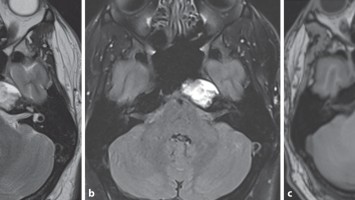

Normaler Verlauf nach Hirntumor?

Der Fall eines 52-jährigen Mannes verdeutlicht, warum es sinnvoll ist, Diagnosen zu hinterfragen. Er kam mit seinem Betreuer zur Kontrolle nach einem Anfallsrezidiv. Anamnestisch lag ein Astrozytom vor, das bereits mehrfach operiert wurde. Auffällig waren seine Schwerhörigkeit und sein unsicherer Gang.

Kutane Arzneimittelreaktion/© Hötzenecker, W., Heimlich-Manöver/© Widmer, N; Heimes, D / all rights reserved Springer Medizin Verlag GmbH, Aufbau bei einer endoskopische Mittelohrchirurgie/© Mir-Salim P., Berlin, Wespen auf Stein/© merlion / Getty Images / iStock (Symbolbild), Schilddrüse einer Patientin wird untersucht/© Werner / stock.adobe.com (Symbolbild mit Fotmodellen), Volumetrie des Bulbus olfactorius/© Keweloh S.. et al. doi.org/10.1007/s00106-025-01650-z unter CC-BY 4.0, Augen und Nase einer Frau/© AlexanderFord / Getty Images / iStock (Symbolbild mit Fotomodell), Eine ältere Frau schaut in die Ferne/© RgStudio / Getty Images / iStock (Symbolbild mit Fotomodell), Transnasales Ösophagoskop/© F. Michel, Seeheim-Jugenheim, Ex vivo konfokales Laserscanmikroskopiebild eines Morbus Bowen/© Grunewald S et al. / all rights reserved Springer Medizin Verlag GmbH, Einweckglas mit Hering/© FoodieMedia / Getty Images / iStock (Symbolbild), Zwei Injektionspens mit Semaglutid/© Kassandra / Stock.adobe.com, Gewitter mit Blitzschlag/© solarseven / Getty images / iStock, Ulzerative Form des oralen Lichen planus/© Abdusalamov K. et al. doi.org/10.1007/s00105-025-05540-x unter CC-BY 4.0, Otitis externa/© Dr. P. Marazzi / Science Photo Library (Symbolbild), VMAT-Bestrahlungsplan einer definitiven Radiochemotherapie eines linksseitigen, lokal fortgeschrittenen Tonsillenkarzinoms/© Schnellhardt, S et al. / all rights reserved Springer Medizin Verlag GmbH, Frau hustet/© Suzi Media Production / Getty Images / iStock (Symbolbild mit Fotomodell), Tympanometrie bei einer Frau/© Viacheslav Yakobchuk (Symbolbild mit Fotomodell), Stimmlippeninjektion in der HNO-Praxis/© Markus Hess, Mann erhält eine Spritze im Gesicht/© Alvaro / Stock.adobe.com (Symbolbild mit Fotomodell), Ein Arzt sprüht ein antimikrobielles und entzündungshemmendes Spray in den entzündeten Hals eines Mädchens./© HENADZY / Stock.adobe.com (Symbolbild mit Fotomodell), Junger Mensch bekommt Spritze verabreicht/© mapo / Getty Images / iStock (Symbolbild mit Fotomodellen), Bestrahlungsplans einer Wirbelsäulenmetastase eines oligometastasierten Prostatakarzinoms/© Springer Medizin Verlag GmbH, Cholesterolgranulom im MRT/© Frederik F/ all rights reserved Springer Medizin Verlag GmbH, Schimmelbefall an der Wand/© Bigy / Stock.adobe.com (Symbolbild), Rasterelektronenmikroskopische Aufnahme von Nanopartikeln/© Hansen S. et al. doi.org/10.1007/s00106-025-01633-0 unter CC-BY 4.0, Medulläres Schilddrüsenkarzinom linker Schilddrüsenlappen in der Sonographie/© Lorenz K et al. / all rights reserved Springer Medizin Verlag GmbH, Sonnenhüte (Echinacea)/© Wieland Teixeira / Getty Images / iStock (Symbolbild mit Fotomodell), Körperstereotaxie einer Lebermetastase im Segment VIII am MR-LINAC/© Ehret, F. et al. / all rights reserved Springer Medizin Verlag GmbH, Eine ältere Frau riecht an einem Basilikumblatt/© Halfpoint / Stock.adobe.com (Symbolbild mit Fotomodell), Mann hustet/© kostyha / stock.adobe.com (Symbolbild mit Fotomodell), Titel/© J. Hornung, Erlangen, Senior hält sich vor Schmerzen an den Hals/© brizmaker / Getty Images / iStock (Symbolbild mit Fotomodell), Chor von älteren Menschen/© Highwaystarz-Photography / Getty (Symbolbild mit Fotomodellen), Eine junge Frau spült sich mir einer Nasenspülung die Nase/© puhhha / Getty Images / iStock (Symbolbild mit Fotomodell), Kleiner Junge mit Pille auf der Zunge/© redpepper82 / stock.adobe.com (Symbolbild mit Fotomodell), Frau mit Kopfschmerzen/© MaximFesenko / Getty Images / iStock (Symbolbild mit Fotomodell), Normaler Verlauf nach Hirntumor?/© Wolfgang Freund, Szintigraphie der Schilddrüse mit zwei Knoten/© AniphaeS / Getty Images / iStock, Patient mit Bauchschmerzen beim Arzt/© anon / Stock.adobe.com (Ausschnitt; Symbolbild mit Fotomodellen), Mann erleidet Schwindel/© Tunatura / Getty Images / iStock (Symbolbild mit Fotomodell), Ärztin untersucht ältere Frau/© peopleimages.com / stock.adobe.com (Symbolbild mit Fotomodellen), Infusion/© georgeoprea9 / Getty Images / iStock, Frau wird Blut abgenommen/© andresr / Getty Images / iStock (Symbolbild mit Fotomodellen), Junge Ärztin vor einem Triage-Zelt/© Milos / Stock.adobe.com (Symbolbild mit Fotomodell)